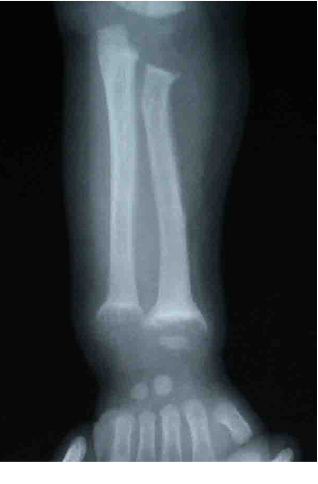

4. 典型腕关节X片检查

长骨钙化带消失;干骺端呈毛刷样、杯口状改变;骨骺软骨盘增宽(>2mm);骨质稀疏,骨皮质变薄。